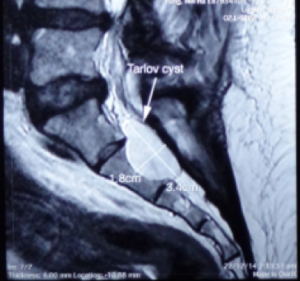

3.4 X 1.8 cm 骶骨第二節骶管襄腫

骶管襄腫一般生長於骶骨的第一節至第三節,內裹充滿了腦脊液, 襄腫可逐漸增大導致馬尾神經線被壓迫, 引起神經根發炎或產生脊髓病變及令骨性結構也被侵入破壞.。磁力共振檢查可清楚分辨骶管襄腫的位置,大小及與硬脊膜和神經根的關係。

一般細小的骶管襄腫多數不會引起任何問題.但如病人的徵狀引起神經缺損而嚴重地影響日常生活, 手術介入可能是最好的選擇。 手術經腦神經外科醫生處理,以微創手術,將襄腫抽吸腦脊液,再封堵阻止脊液進入,然後拿取病人身體的脂肪或肌肉來填塞襄腫空間。( 圖ー , 圖ニ)

3.4 X 1.8 cm 骶骨第二節骶管襄腫

圖一